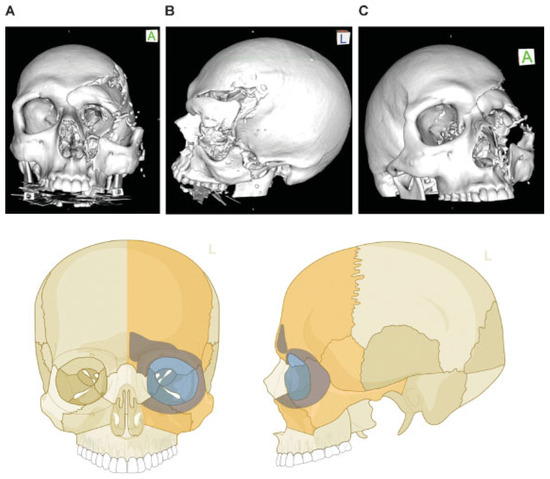

Figure 10.

Lateral cranio-orbito-facial Injury: fronto-spheno-zygomatico-orbital fracture. Imaging: Three-dimensional (3D) computed tomographic scans (A) frontal view, (B) lateral view left, and (C) oblique lateral view right. Narrative description: Large-sized fragment of left frontotemporal vault and skull base including all four orbital walls. Displaced (caudolateral) monofragment of left zygoma in continuity with infraorbital rim and antral wall, leading to an extreme diastasis of left lateral orbital wall, multifragmentation along the posterior articulations of the zygoma and in the frontotemporal transition (greater wing of sphenoid). (D) Level 3 Code: 92 m.Omil.I1i.Z1li - 93 m.Oas.M0.A0.S1 - 94 m.F1m, Orbit (left): R(slim).W1(slim)2(slim).A(slm). This case example CMTR-92-106 is made available electronically for viewing using the AOCOIAC software at www.aocmf.org/classification.